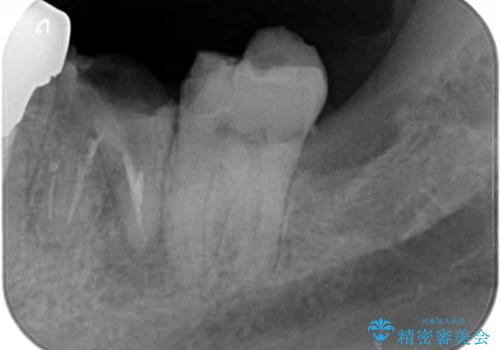

- 下顎左右の奥歯を治療途中で放置してしまっているとのことで来院された患者様です。

欠損部はインプラントによる補綴治療を、土台の外れてしまった歯は、根管治療を行った上で、補綴治療を行うこととしました。

- 根管治療により痛みや腫れがひかない事や、術後に痛みや腫れが生じる事、治療によるファイル破折やパーフォレーションなどの偶発症、術後の歯根破折を生じる可能性もあります